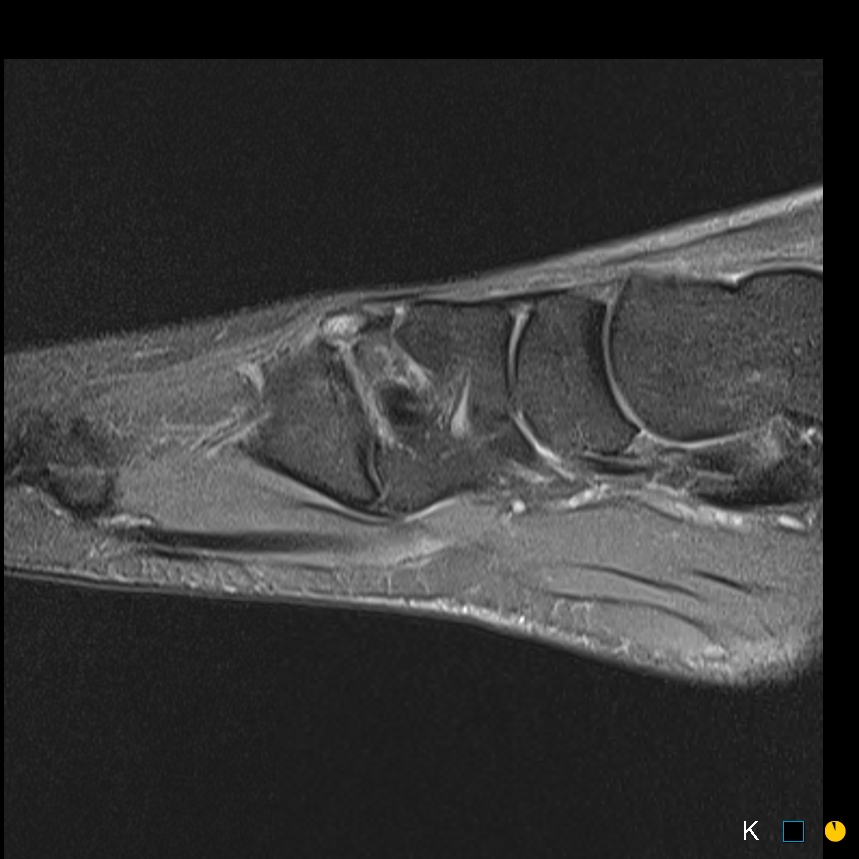

Sprinter. Dorsal midfoot pain

Symptomatic os intermetatarseum

Case reports of symptomatic os intermetatarseum in athletes

Symptoms may relate to compression medial br DPN